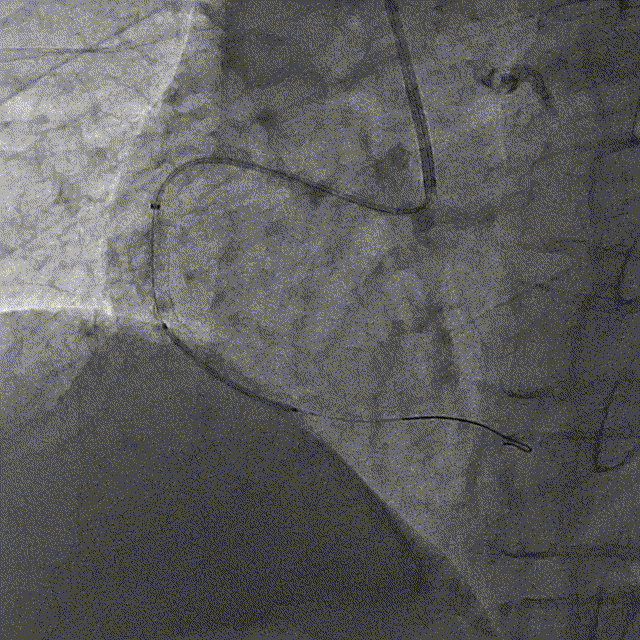

冠脉造影

冠脉造影结果:LM外膜钙化,内膜不光滑,中段狭窄90%,TIMI3级。LCX外膜钙化,内膜不光滑,TIMI3级。RCA外膜钙化,内膜不光滑,近段狭窄80%,中段狭窄90%,可见破损斑块,TIMI3级。